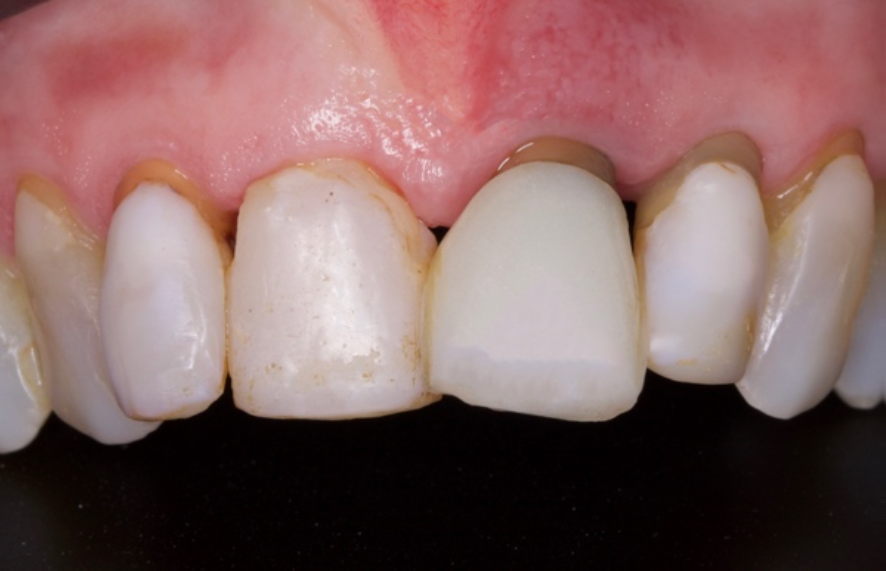

O objetivo deste relato de caso é mostrar a utilização do implante de diâmetro reduzido em região anterior de maxila com limitação óssea, respeitando a anatomia do processo alveolar e consequentemente utilizando um componente angulado para corrigir a posição da saída do parafuso para confecção de uma prótese aparafusada.

Conforme discutido na literatura, a colocação imediata de implantes na zona estética requer que o clínico tenha conhecimento e experiência em diversas áreas. Isso inclui diagnóstico estético, técnicas de extração minimamente invasivas, procedimentos cirúrgicos plásticos orais (por exemplo, enxerto de tecidos duros e moles) e colocação de implantes tridimensionais (3D) precisos com o uso de um implante mais estreito (3,3 mm a 4,3 mm), o que garante um espaço vestibular de pelo menos 2 a 3 mm adjacente à parede do alvéolo bucal intacto. Isso pode ser pré-planejado com uma análise cuidadosa através de exames de imagem para uma melhor compreensão do plano restaurador. O uso de técnicas avançadas de imagem, como a tomografia computadorizada de feixe cônico (CBCT), pode auxiliar no planejamento preciso do tratamento e na colocação do implante.